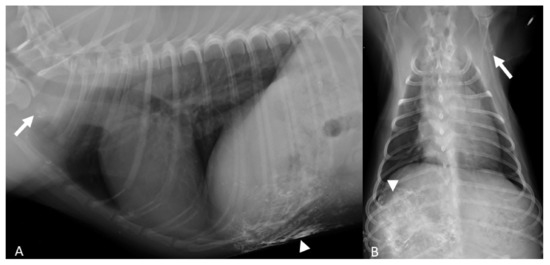

3.2. Lymph Node Drainage